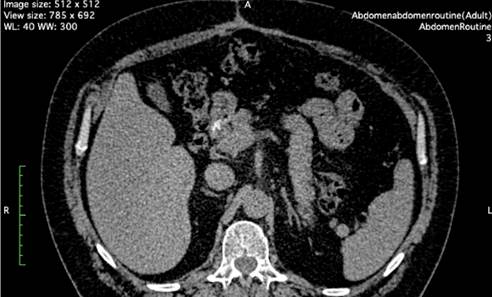

Клинический случай 2. Мужчина 37 лет оперирован по поводу послеоперационной грыжи, образовавшейся после множества операций, выполненных в связи с деструктивным панкреатитом. Также перенес резекции кишечника. Данные компьютерной томографии (КТ) приведены на рис. 8.

Рис. 8. КТ второго пациента перед операцией. Белой линией обозначены грыжевые ворота